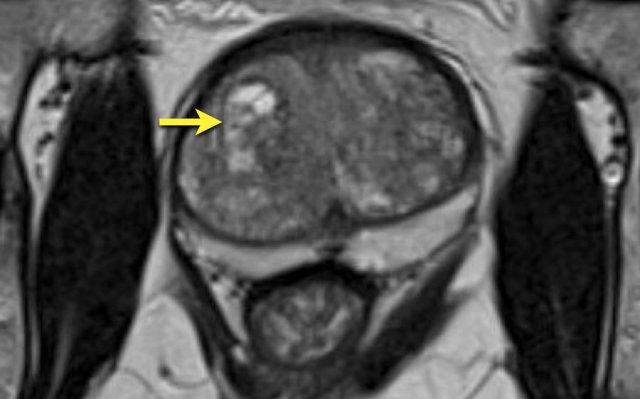

Một tổn thương kích thước 16 mm (không hiển thị phép đo) được phát hiện, nằm ở phía sau vùng ngoại vi của phần giữa tuyến tiền liệt bên phải.

Tổn thương này được xếp vào phân loại PI-RADS 5, dựa trên giảm tín hiệu rõ rệt trên ADC và tăng tín hiệu rõ rệt trên DWI (điểm 5 – chuỗi xung chính), đối chiếu với giảm tín hiệu rõ rệt trên chuỗi xung T2W (điểm 5).

Điểm Gleason là 3+4, cho thấy nguy cơ trung bình của một ung thư có tính xâm lấn cao.

Tổn thương không tiếp xúc với vỏ bao giả và không có dấu hiệu xâm lấn ra ngoài tuyến tiền liệt.